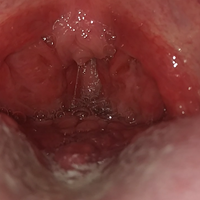

¿Tengo VPH? Bolitas atrás de la lengua